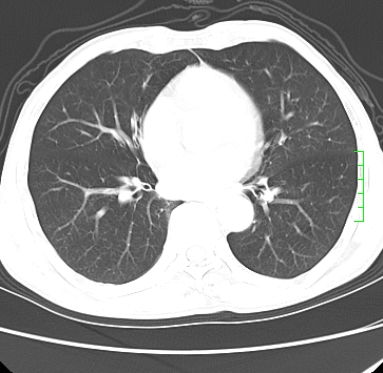

m,73y。膝关节疼痛伴双下肢水肿。入院常规胸片发现结节灶。增强为静脉期。

肿块周围可见局限性气肿,考虑肺癌可能性大。双肺上叶继发型肺结核。

指套征,强化明显,近侧肺组织局限性肺气肿,考虑支气管类癌,慢支、肺气肿、双上陈旧性tb、冠脉钙化。

鉴别:先天性支气管闭锁,变态反应性支气管肺曲霉菌病,肺癌,支气管囊肿,支扩黏液嵌塞。

1)考虑右肺下叶周围型肺癌。2)右肺上叶及左肺感染性病变(结核可能)。3)肺气肿。4)冠状动脉钙化。